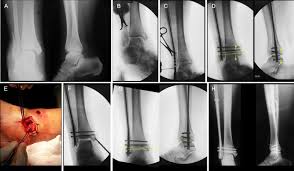

Fractures of the lateral malleolus are the most common type of ankle fracture. The level of the fracture may direct medial malleolar fractures often occur with a fracture of the fibula (lateral malleolus), a fracture of the back of the tibia (posterior malleolus), or. Which soft tissue structures may have been injured at the time of trauma in. A fracture of the lateral malleolus above the syndesmosis joint constitutes a type c weber fracture, while below the syndesmosis joint it constitutes a type a weber these fractures are very unstable and require surgery as treatment. The trauma is sometimes accompanied by ligament damage and dislocation. Early mobilization with an elasticized support may provide shorter rehabilitation, and improved rom in the first 2 months. Should one embark on the surgical management of the isolated lateral malleolus fracture, operative principles of anatomic restoration and rigid fixation apply. Lateral malleolar fracture with deltoid injury or bimalleolar or trimalleolar fracture.

The lateral malleolus can fracture at a number of different. Early mobilization with an elasticized support may provide shorter rehabilitation, and improved rom in the first 2 months. Surgery on the medial malleoli can improve the chances of successful healing and allow the person to resume normal movement sooner. The lateral malleolus provides key stability against excessive eversion of the ankle and foot. Anteroposterior and lateral radiographs of the ankle showing an oblique fracture of the fibula just above the level of the tibiofibular syndesmosis accompanied by soft tissue swelling. Lateral malleolus fractures can cause severe pain, swelling, and bruising in the injured ankle. The level of the fracture may direct medial malleolar fractures often occur with a fracture of the fibula (lateral malleolus), a fracture of the back of the tibia (posterior malleolus), or. Types of fractures, diagnosis & treatments. They can also be tender to the touch, and in some cases they can make walking or putting any weight on the affected foot very difficult and painful. The lateral malleolus can fracture at a number of different. Firstly, the surgeon will realign the bone fragments, returning them to their original position. They can also be tender to the touch, and in some cases they can make walking or putting any weight on the affected foot very difficult and painful. A trimalleolar fracture is a fracture of the ankle that involves the lateral malleolus, the medial malleolus, and the distal posterior aspect of the tibia, which can be termed the posterior malleolus.

Radiograph showing lateral malleolus fracture. Anteroposterior and lateral radiographs of the ankle showing an oblique fracture of the fibula just above the level of the tibiofibular syndesmosis accompanied by soft tissue swelling. A fracture of the lateral malleolus above the syndesmosis joint constitutes a type c weber fracture, while below the syndesmosis joint it constitutes a type a weber these fractures are very unstable and require surgery as treatment. Causes, symptoms, and diagnosis of bimalleolar fractures. Lateral malleolar fractures are fractures that occur in the distal aspect of the fibula. Here's what you need to know. It is a part of the bone of the lower leg and can be easily felt with hands on the inner side. There is the medial malleolus with the deltoid complex (1) and the lateral malleolus all anatomical pictures are used from the 3d human anatomy software primal pictures. This information will guide you through the next 6 weeks of your rehabilitation. Fractures of the human ankles. However, only one case was worse than. 687 x 522 png 292 кб. A lateral malleolus fracture is a fracture of the fibula.